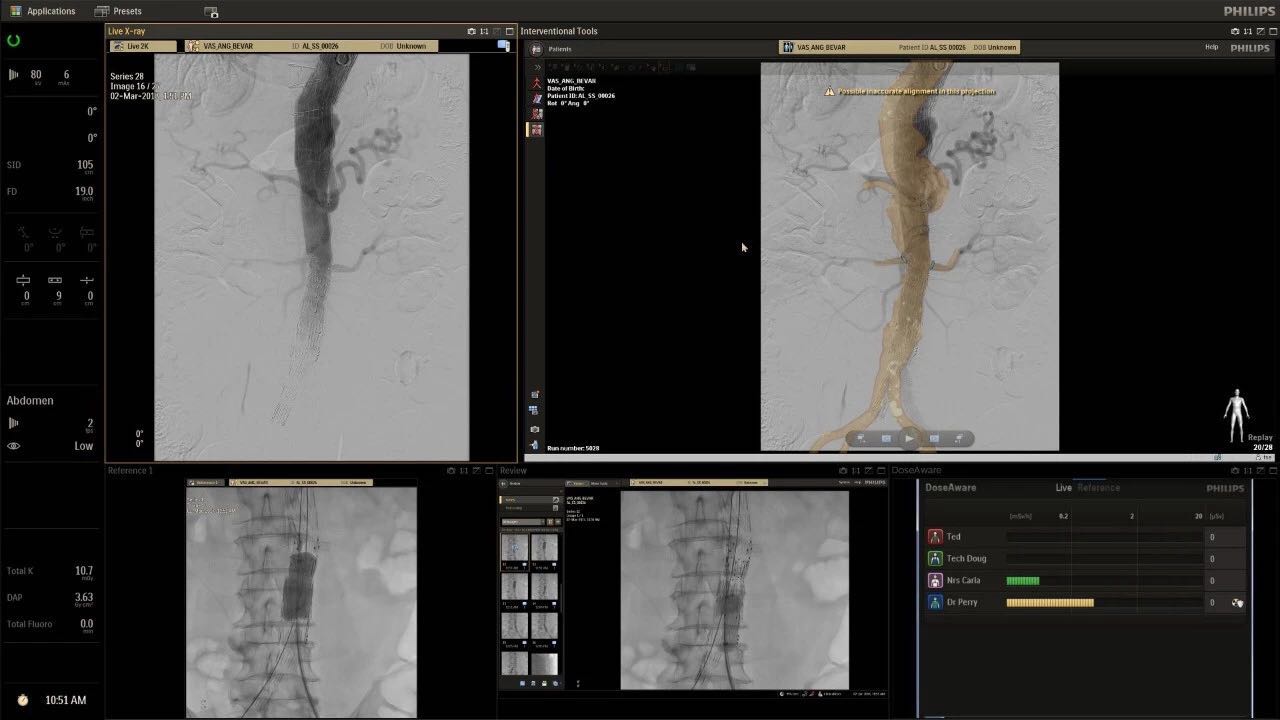

在日益復(fù)雜的干預(yù)期間,臨床醫(yī)生需要快速、輕松地可視化關(guān)鍵解剖結(jié)構(gòu)并確定手術(shù)過程中患者的變化。2019年1月17日,飛利浦宣布推出采用FlexArm的Azurion 7 C20,旨在提高圖像引導(dǎo)程序的定位靈活性。

帶有FlexArm的Azurion 7 C20 包含一系列創(chuàng)新技術(shù),使臨床醫(yī)生可以更輕松地在整個(gè)患者身上進(jìn)行二維和三維成像。當(dāng)臨床醫(yī)生移動(dòng)系統(tǒng)時(shí),圖像光束自動(dòng)保持與患者的對準(zhǔn),允許更一致的可視化并使他們能夠?qū)⒆⒁饬性谥委熒稀?/span>

飛利浦表示,采用FlexArm設(shè)計(jì)的Azurion 7 C20可提供卓越的靈活性和直觀的控制。該系統(tǒng)由智能運(yùn)動(dòng)引擎驅(qū)動(dòng),可在八個(gè)不同的軸上移動(dòng),所有這些軸均由其單個(gè)“Axsys”控制器控制。臨床醫(yī)生的模擬測試表明,該系統(tǒng)有可能顯著減少患者,工作人員和設(shè)備的重新定位,從而改善微創(chuàng)手術(shù)的可及性,包括通過患者手腕進(jìn)入身體的手術(shù)(橈動(dòng)脈入路),并降低患者的風(fēng)險(xiǎn)。無意中拔出電線和管子,以及節(jié)省大量時(shí)間。該系統(tǒng)非常適合混合手術(shù)室(OR),可滿足一個(gè)房間內(nèi)的多種專業(yè)需求,例如手術(shù)和血管內(nèi)手術(shù)的組合。

FlexArm在不少于8軸的情況下旋轉(zhuǎn),從而創(chuàng)建幾乎無限的靈活性來執(zhí)行成像,從頭部到腳部在左側(cè)和右側(cè)進(jìn)行2D和3D可視化。圖像光束保持與患者對齊,允許在旋轉(zhuǎn)或角度期間更好地可視化解剖結(jié)構(gòu)。使用Axsys運(yùn)動(dòng)控制系統(tǒng)輕松操作支架。